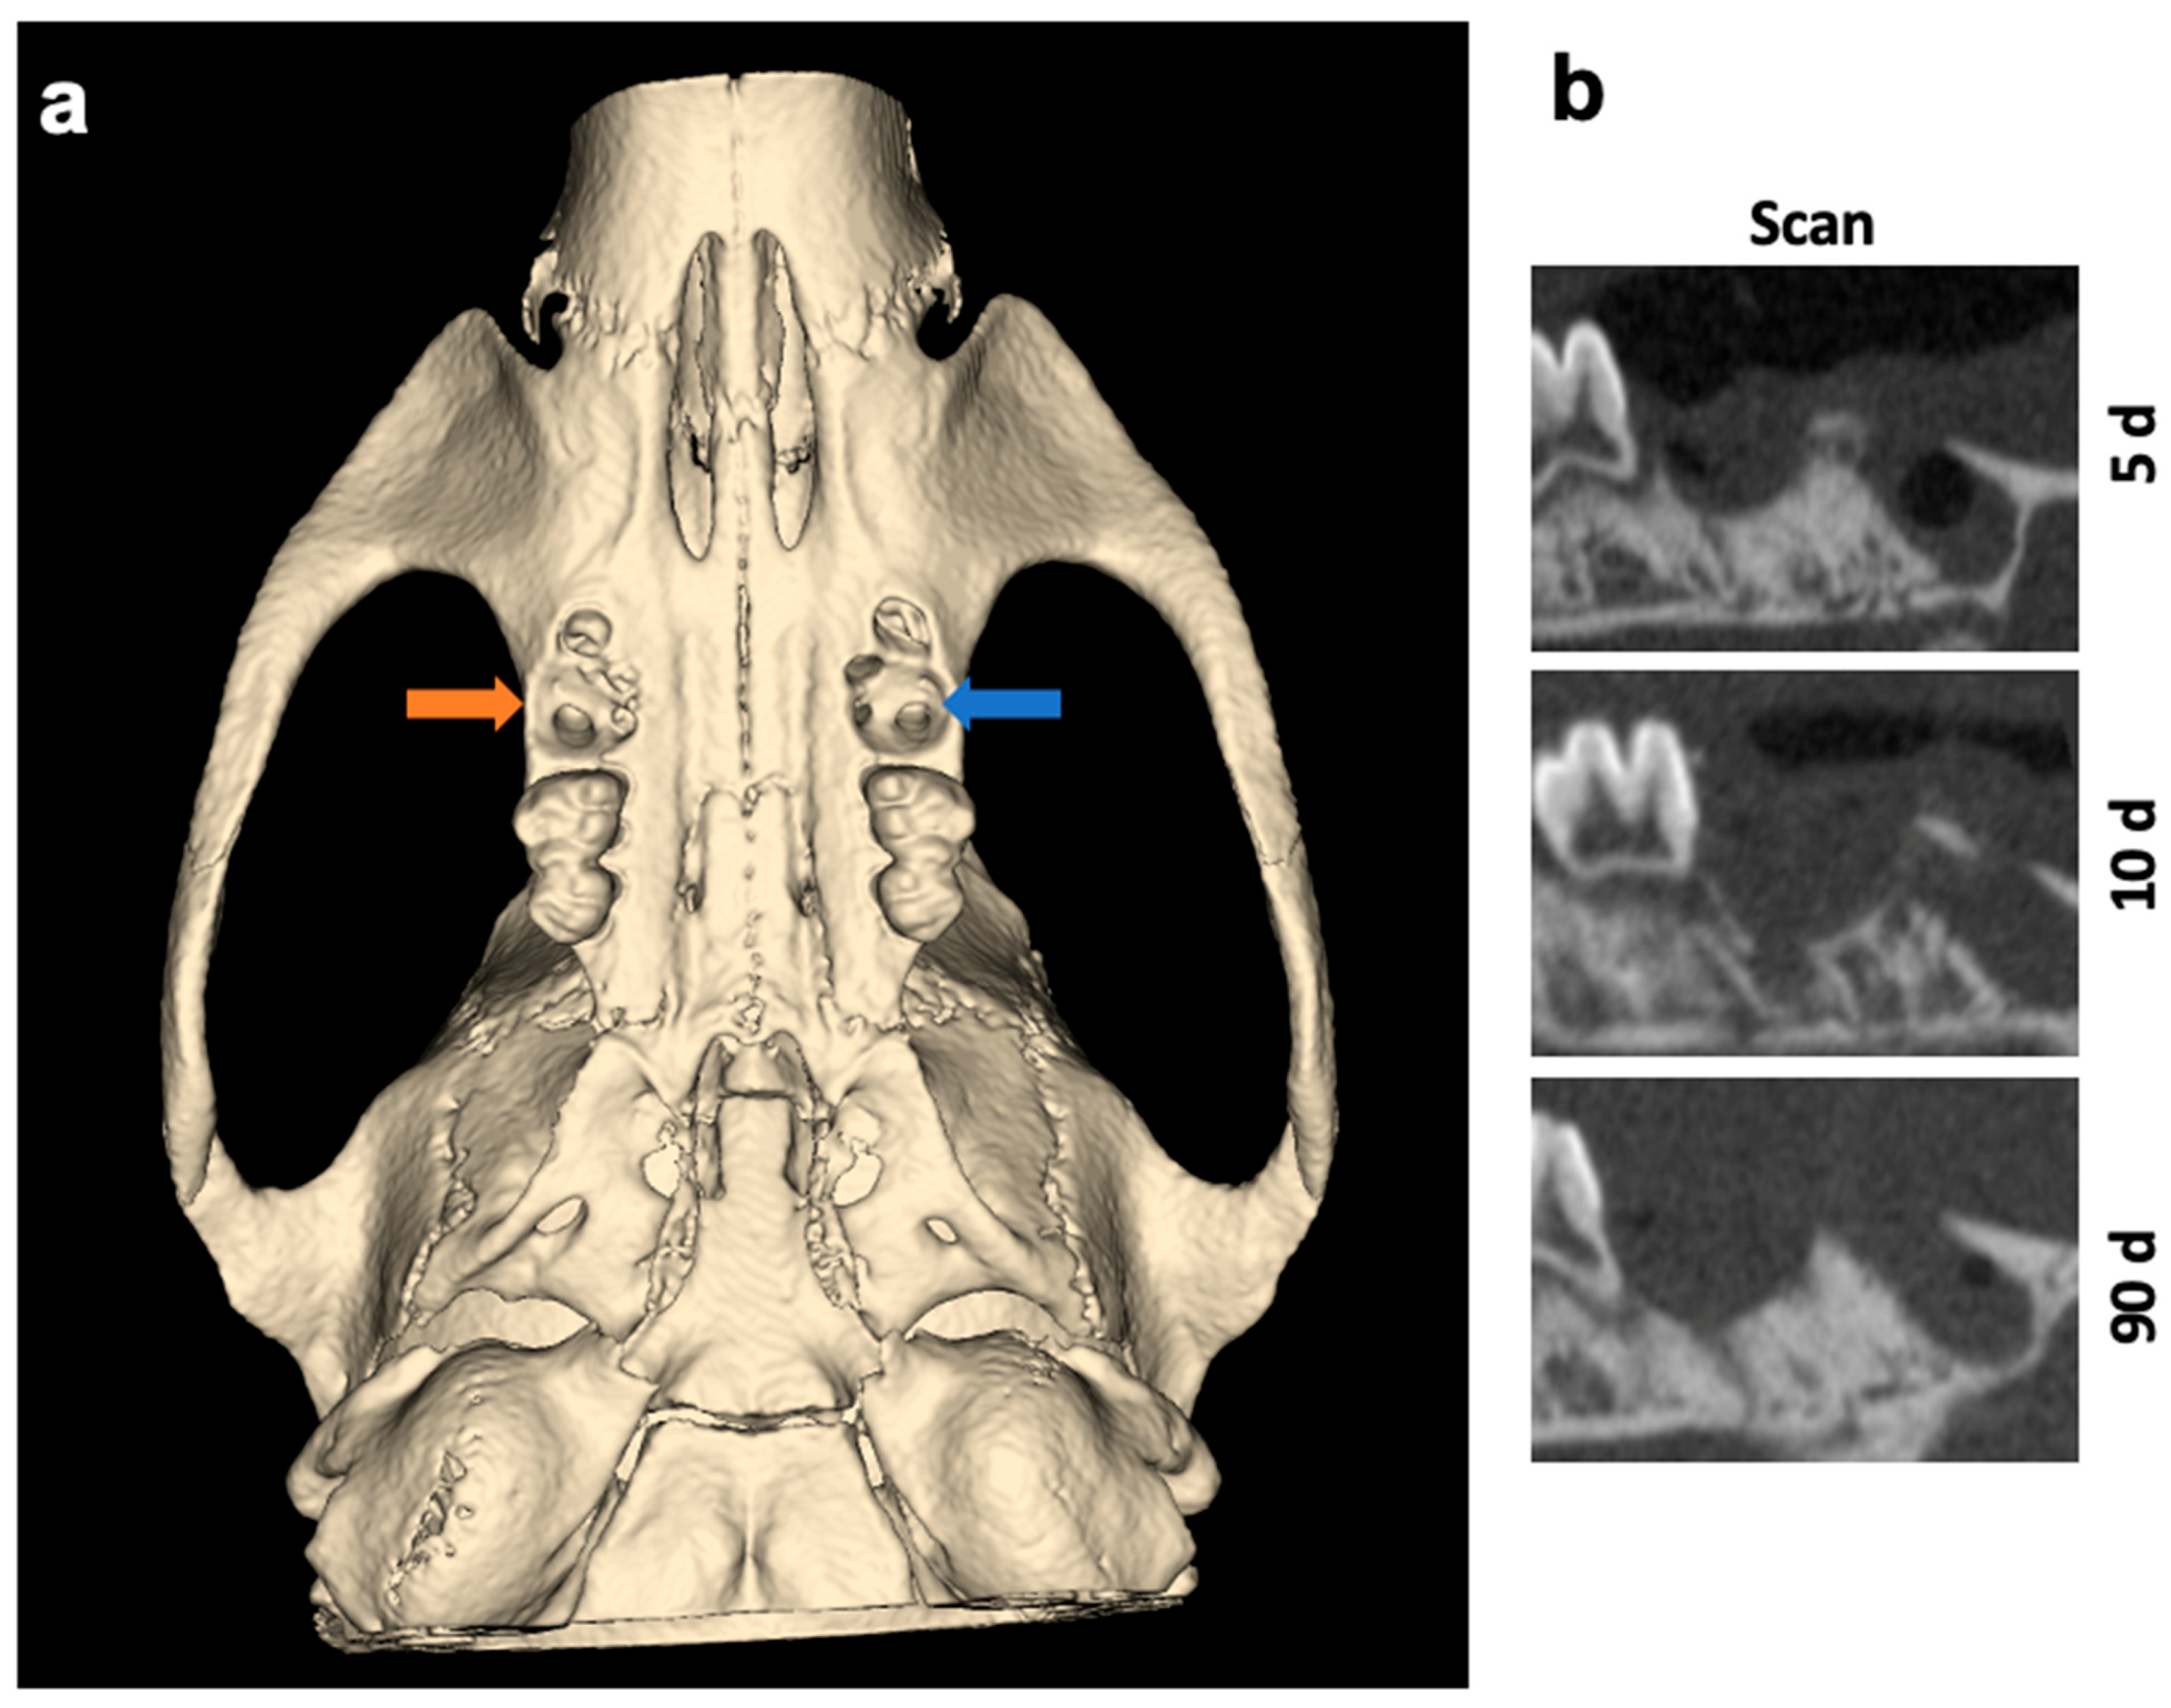

3. Discussion

4.4. Micro-Computed Tomography (µCT) Analysis